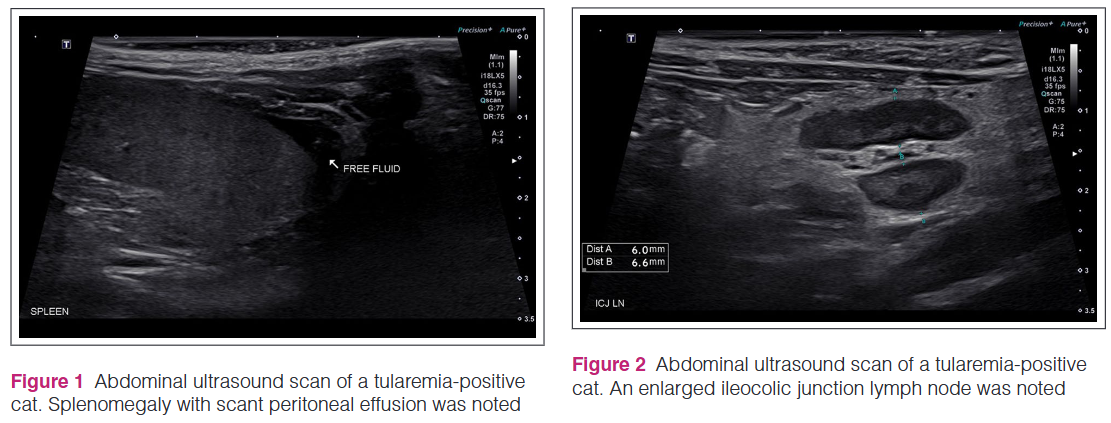

고양이에서의 야토병 주요 증상은 다음과 같다.

증상이 애매하다. 딱보고 알 수 있는 그런 증상은 없고, 길고양이들에서 흔하게 관찰되는 증상 뿐이다. 이를 확진하기 위해서는 PCR 검사를 해야 하는데 한국은 아직 PCR 검사가 잘 되고 있지 않다.

만약 길고양이나 길고양이와 접촉하는 고양이, 생간 등을 먹이는 생식하는 고양이가 고열을 보이며, 구강 궤양이 있거나, 염증성으로 전신 림프절이 관찰되는 증상등을 보인다면 야토병을 감별진단 리스트에 올려야 할것이다.